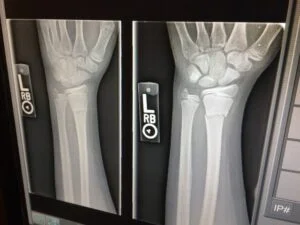

Fractures (Broken Bones)